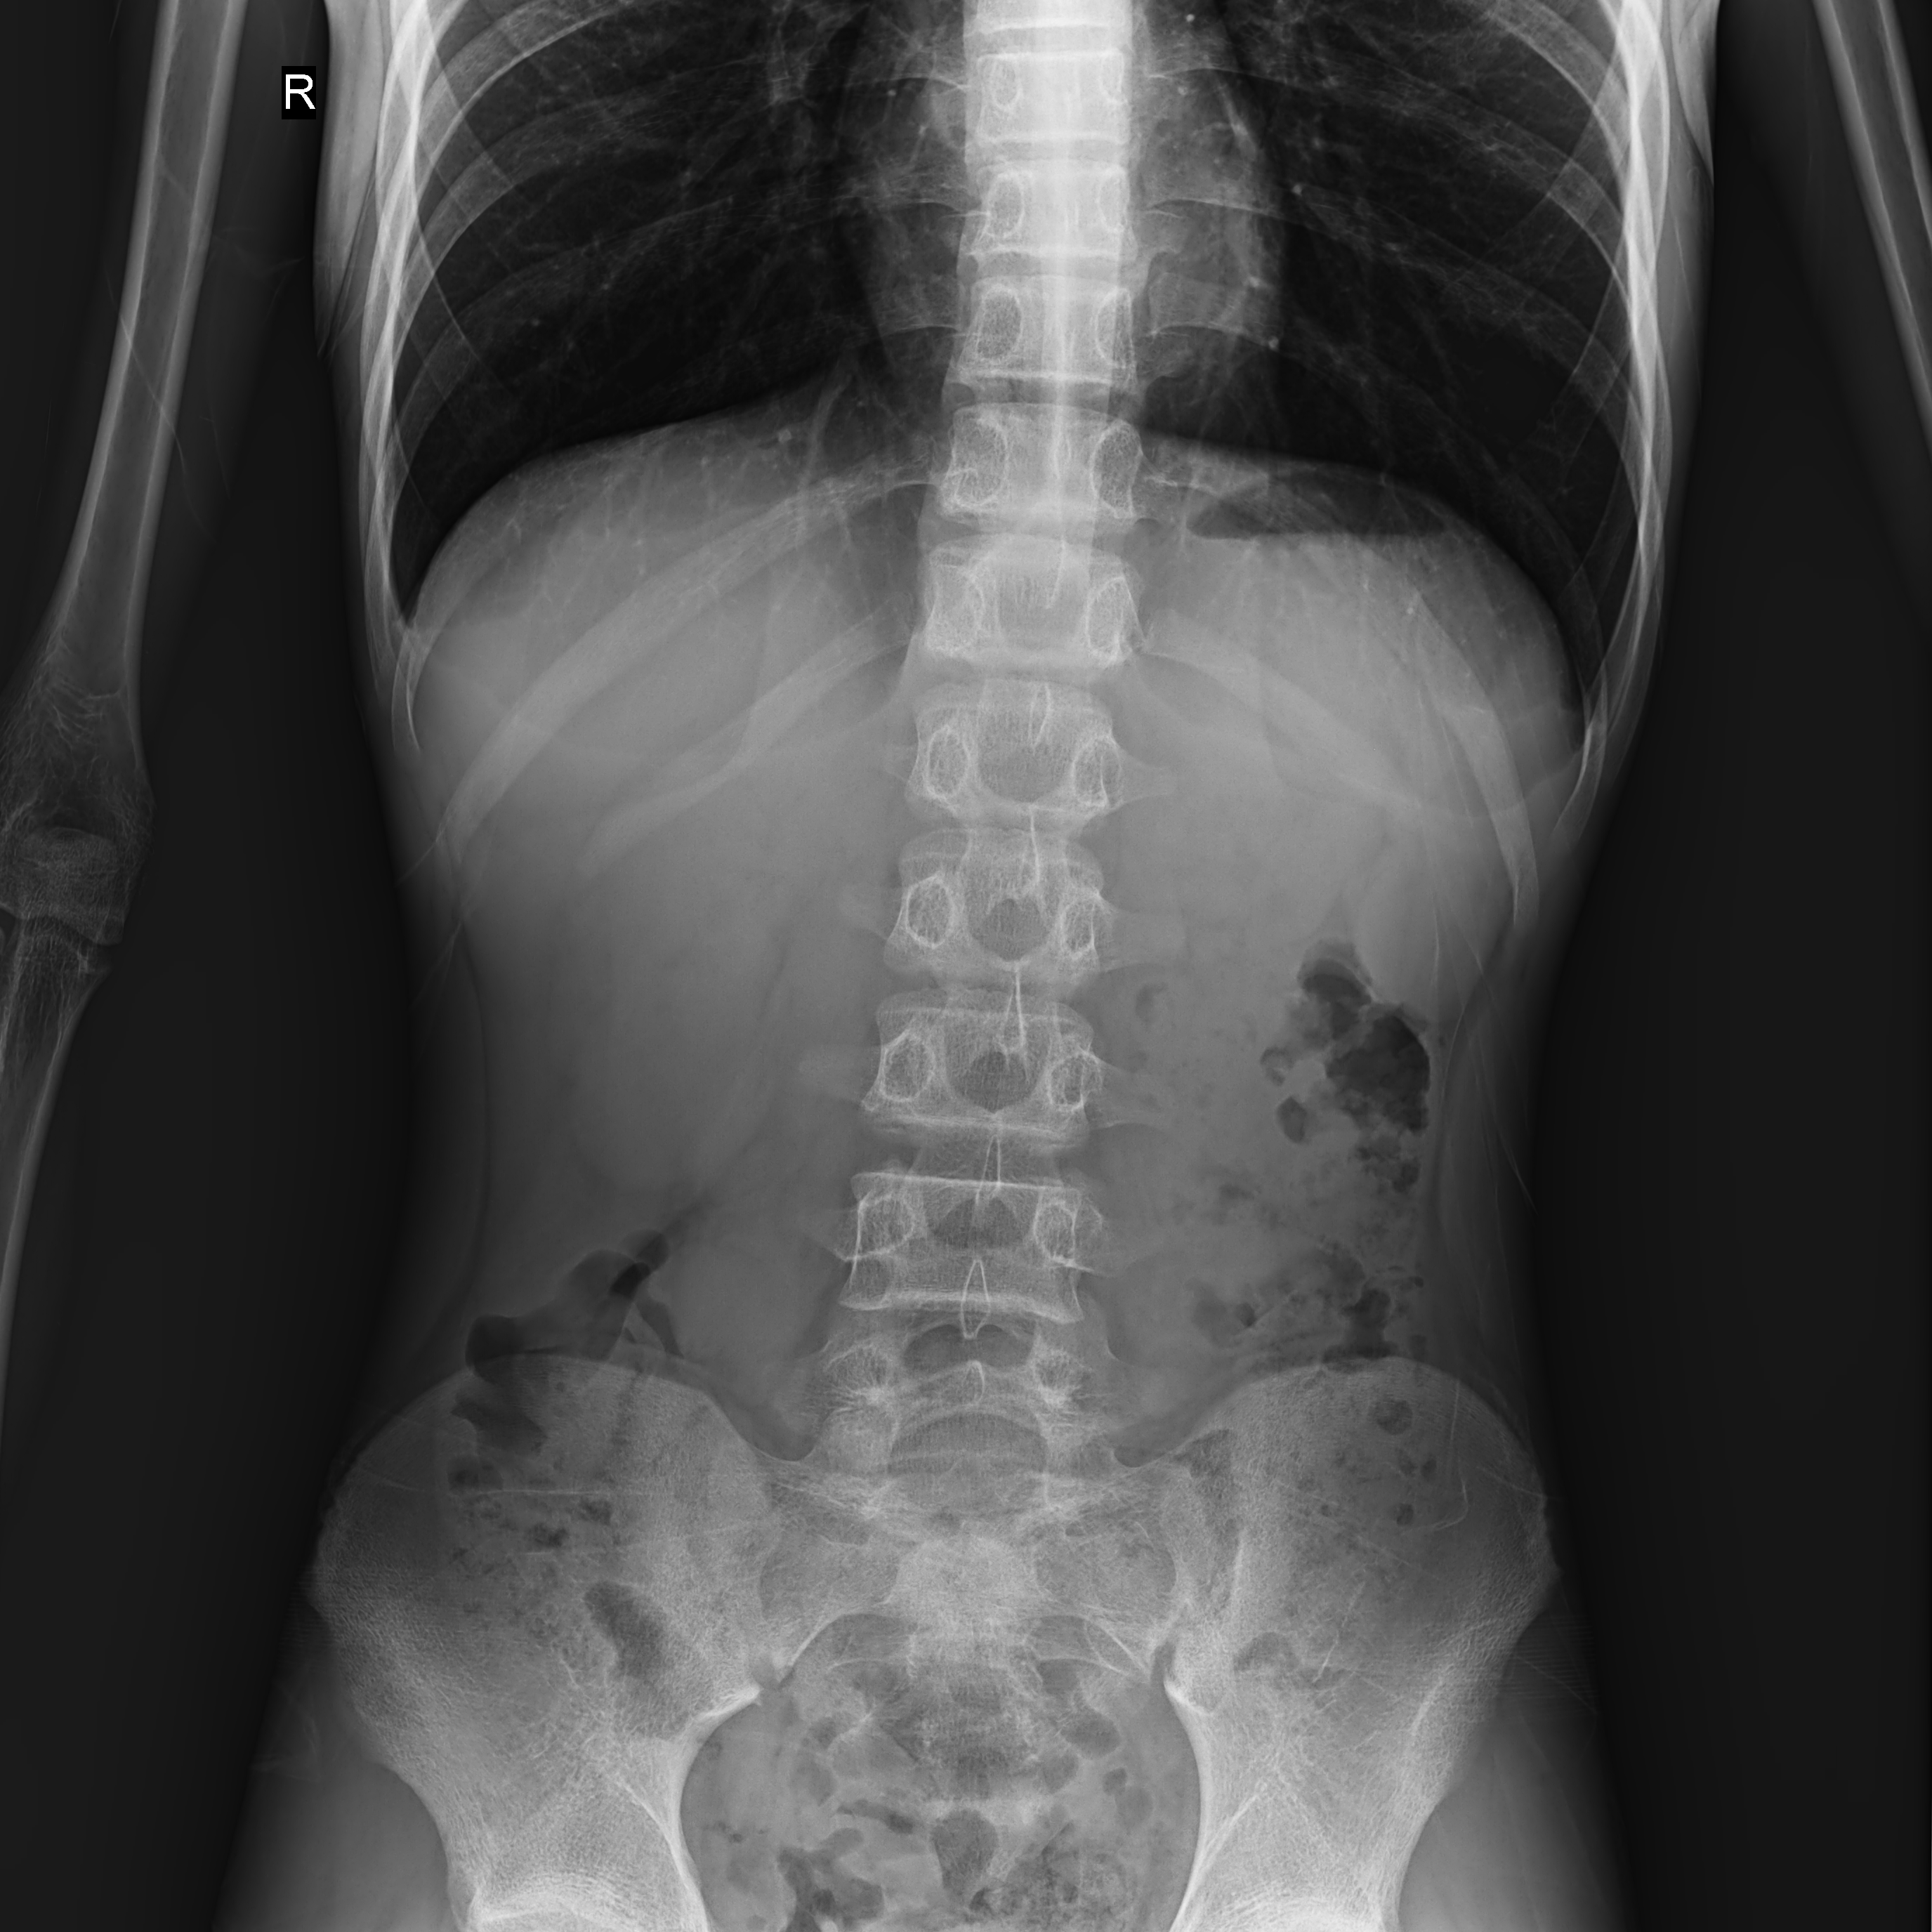

普利德醫療自主研發(fā)的新一代數字化X線(xiàn)透視攝影系統,可應用于DR攝影、數字透視、數字造影以及可視化精準DR拍片等多種臨床X線(xiàn)檢查領(lǐng)域。

● 17*17英寸的超高清像素動(dòng)態(tài)平板探測器,更大的視野范圍,無(wú)需移動(dòng)即可觀(guān)察整個(gè)動(dòng)態(tài)過(guò)程,避免拖尾、噪聲對圖像的影響;

● 高效動(dòng)態(tài)平板技術(shù),圖像不會(huì )有幾何畸變,提供高分辨率和精確的圖像,為醫生臨床診斷提供精準依據;

● 最高幀速可達30幀/秒,動(dòng)態(tài)采集清晰流暢,避免漏診、誤診情況的發(fā)生;

● 在可視過(guò)程或回放過(guò)程中,如發(fā)現疑似病灶,可進(jìn)行毫秒級高清點(diǎn)片,隨時(shí)抓取單幀圖像,精準捕抓病灶。